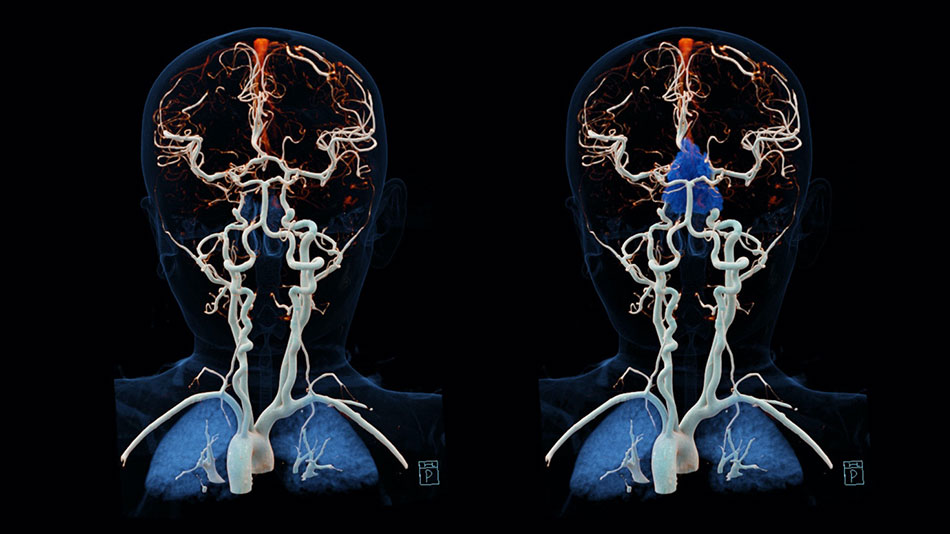

Arteriovenous malformations (AVM)

Arteriovenous malformations are abnormal collections of blood vessels, where arteries are directly connected to veins. Normally blood flows through arteries under high pressure to supply all of the organs of the body including the brain. From the arteries, blood passes through thin-walled capillaries to supply oxygen and nutrients to the tissue of the brain and then enters the veins under low pressure to be carried back to the heart and lungs.

In an AVM, the blood flows from the arteries directly to the veins. There is no capillary bed. Without a capillary bed, the AVM blood vessels have an increase in flow and blood pressure. Over the years this causes them to dilate and become thin-walled, and more likely to break and bleed.

An AVM can cause headache, weakness, numbness, visual problems, or seizures. Patients often first show symptoms when there is a bleed or rupture from one of the blood vessels making up the AVM.

An AVM is often diagnosed with a CT scan or MRI. A patient usually requires an angiography to then fully identify the anatomy of the AVM and make decisions about treatment.

AVMs may be treated using three different treatment methods. These methods are embolization, surgery and radiation therapy or radiosurgery.

Endovascular treatment of AVMsis available at FV Hospital. One innovative form of treatment involves use of a “super glue” substance introduced via a tiny catheter to reduce the size of the AVM and facilitate further microsurgical or radiation treatment. In some cases, it is possible to completely block off and cure the AVM with endovascular treatment alone.

Aneurysms are bulging areas of weakened arteries. Arterio-venous malformations are tangles of thin-walled blood vessels. The danger with both of these conditions is that they can rupture and cause haemorrhage, which may lead to stroke, brain damage or death

We use the latest diagnostic imaging, such as CT angiogram and catheter-based conventional angiography as well as CT angiography which avoids the risks of catheter techniques, to quickly and accurately diagnose your condition. Our treatments for aneurysms can include open operation (clipping), which involves placing a clamp on the neck of the aneurysm. In addition, we offer non-surgical endovascular treatments